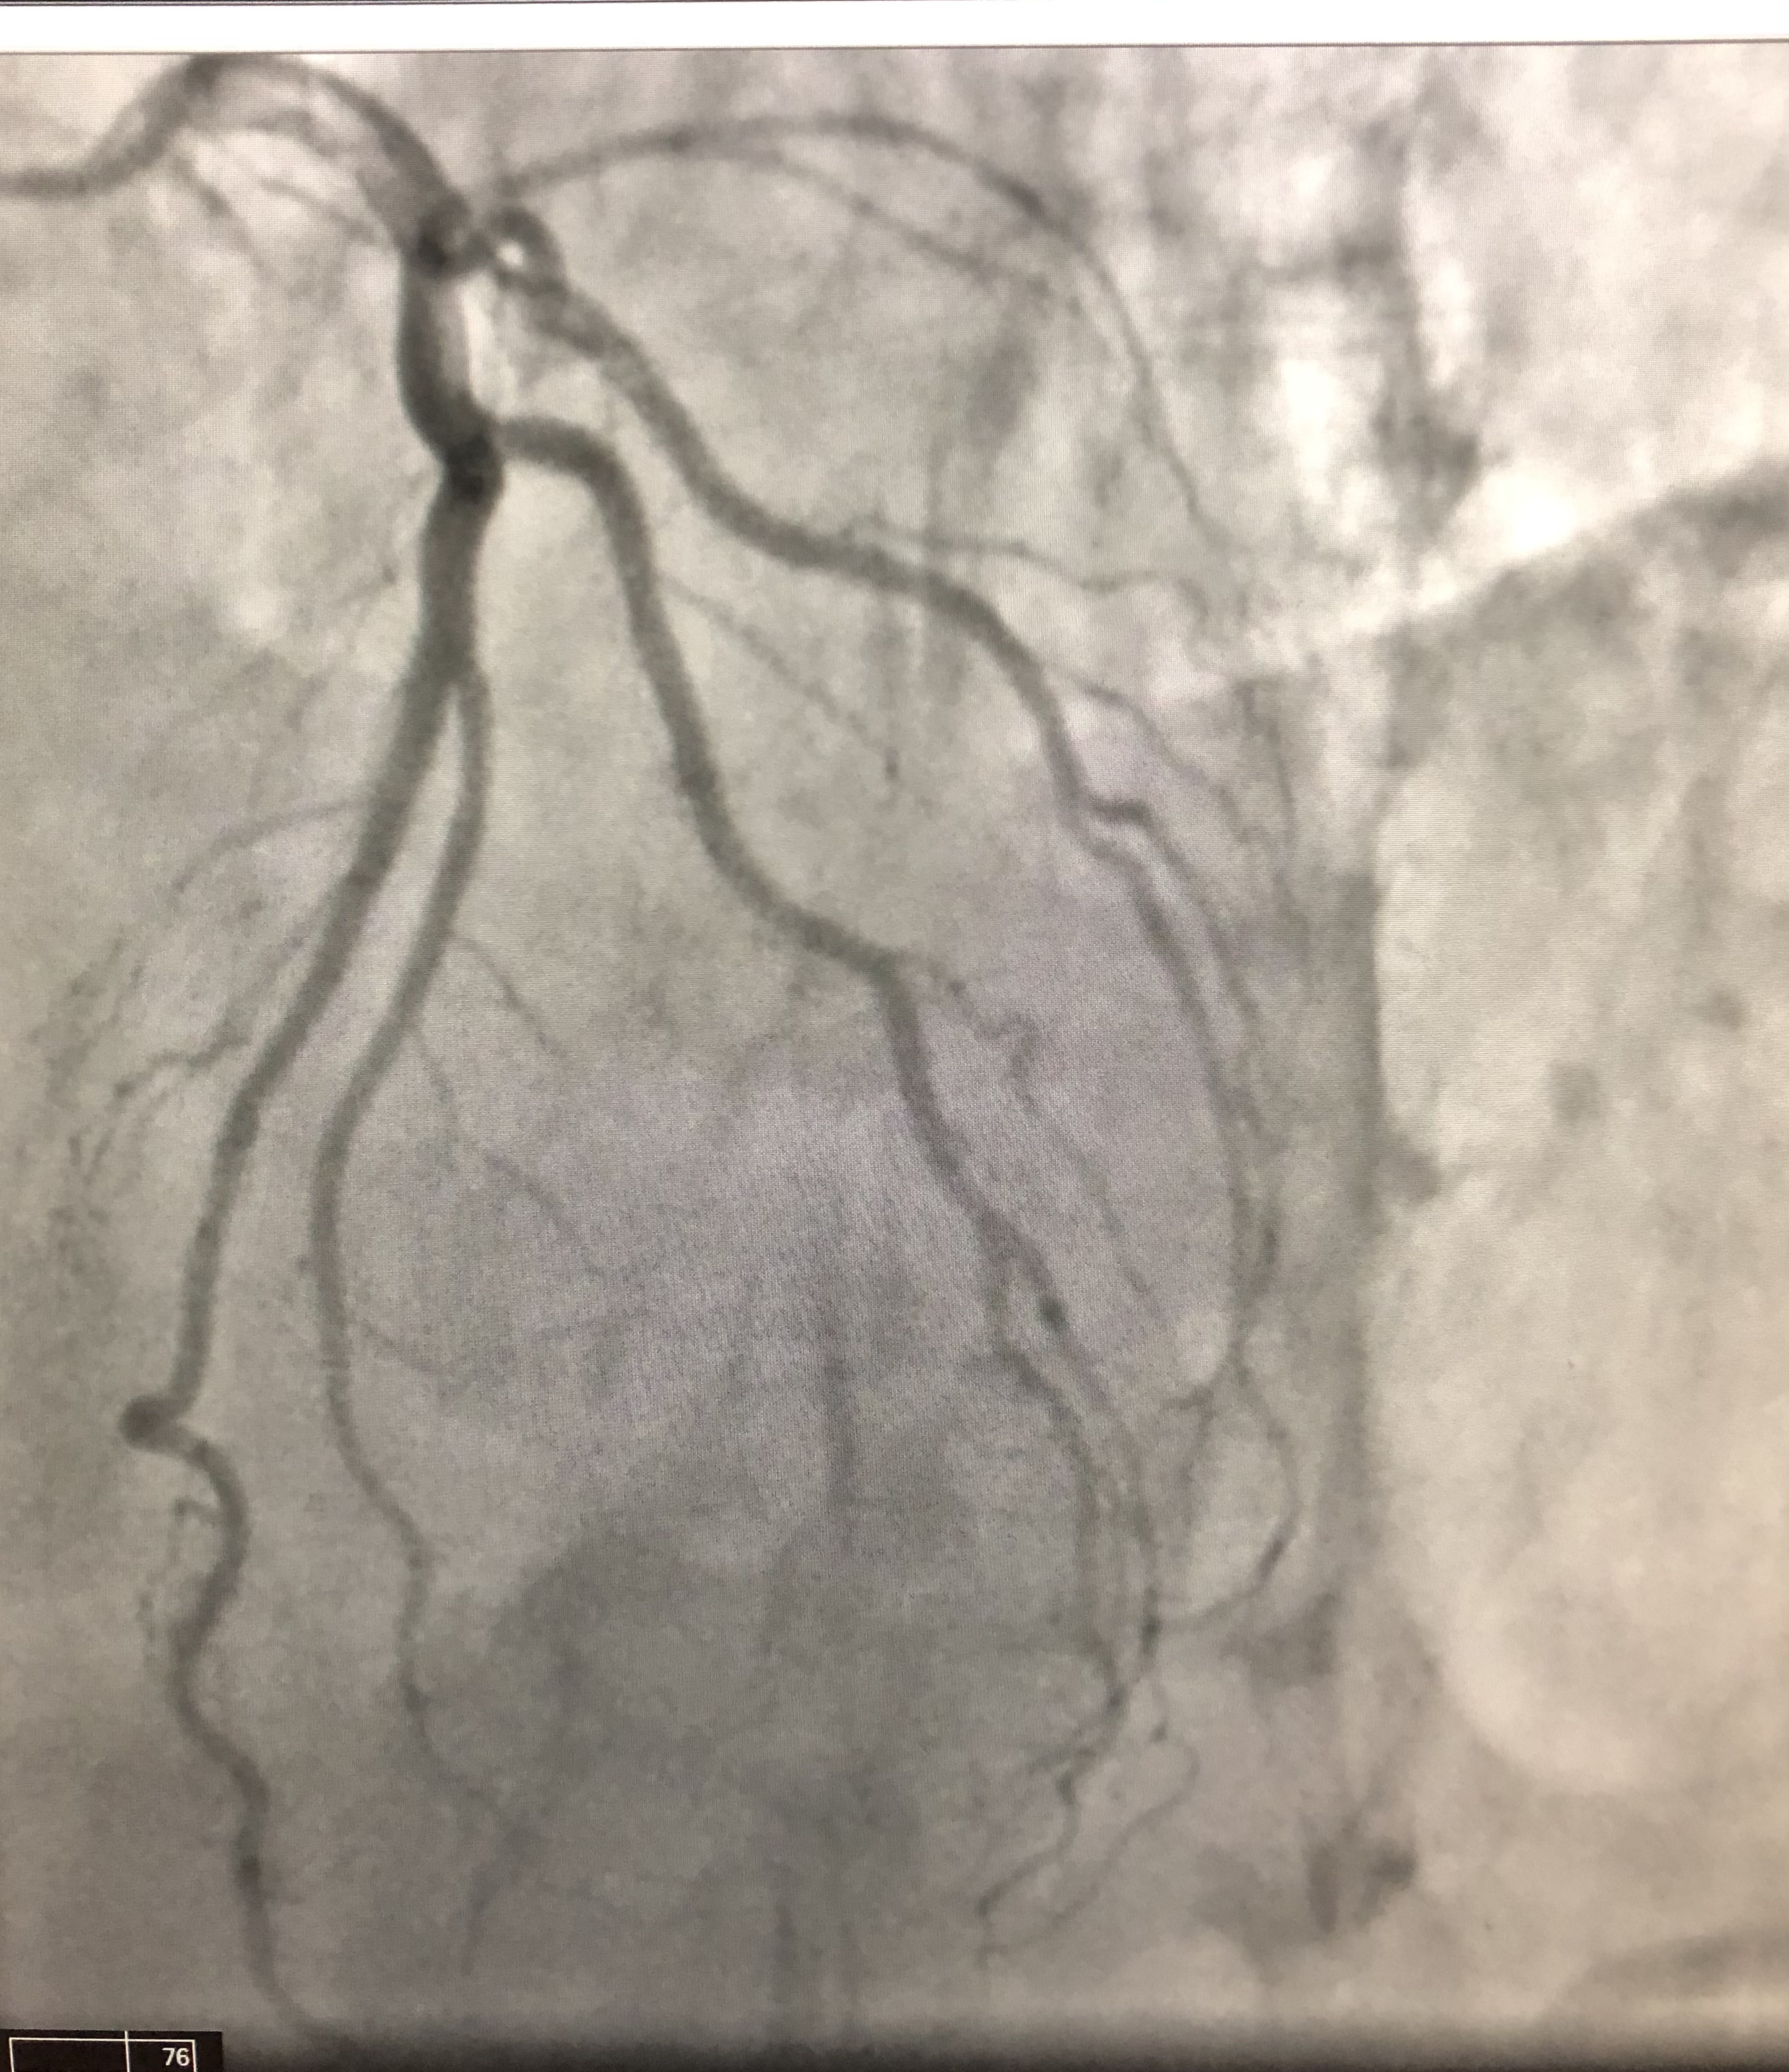

A 72-year-old Black man presented to the clinic with subjective fever, severe fatigue, chest tightness, and dry cough for the previous 3 days. His history was significant for hypothyroidism, and he was a...

01/02/2023